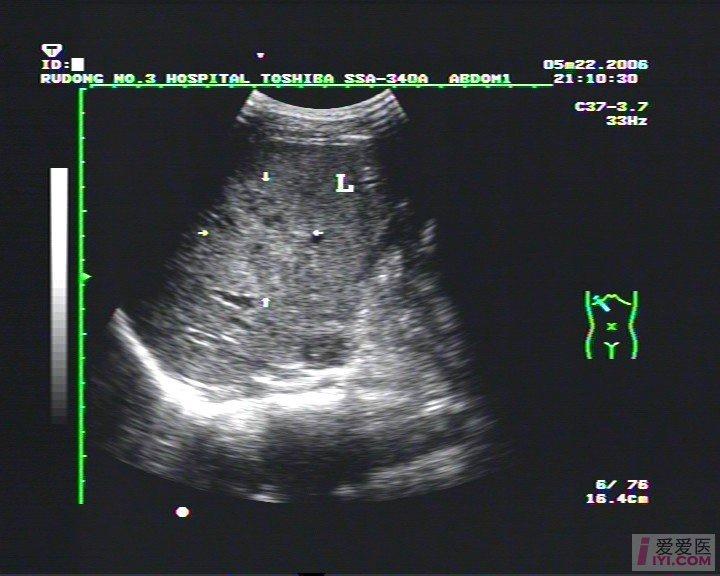

【读片】肝挫伤

右肝内血肿